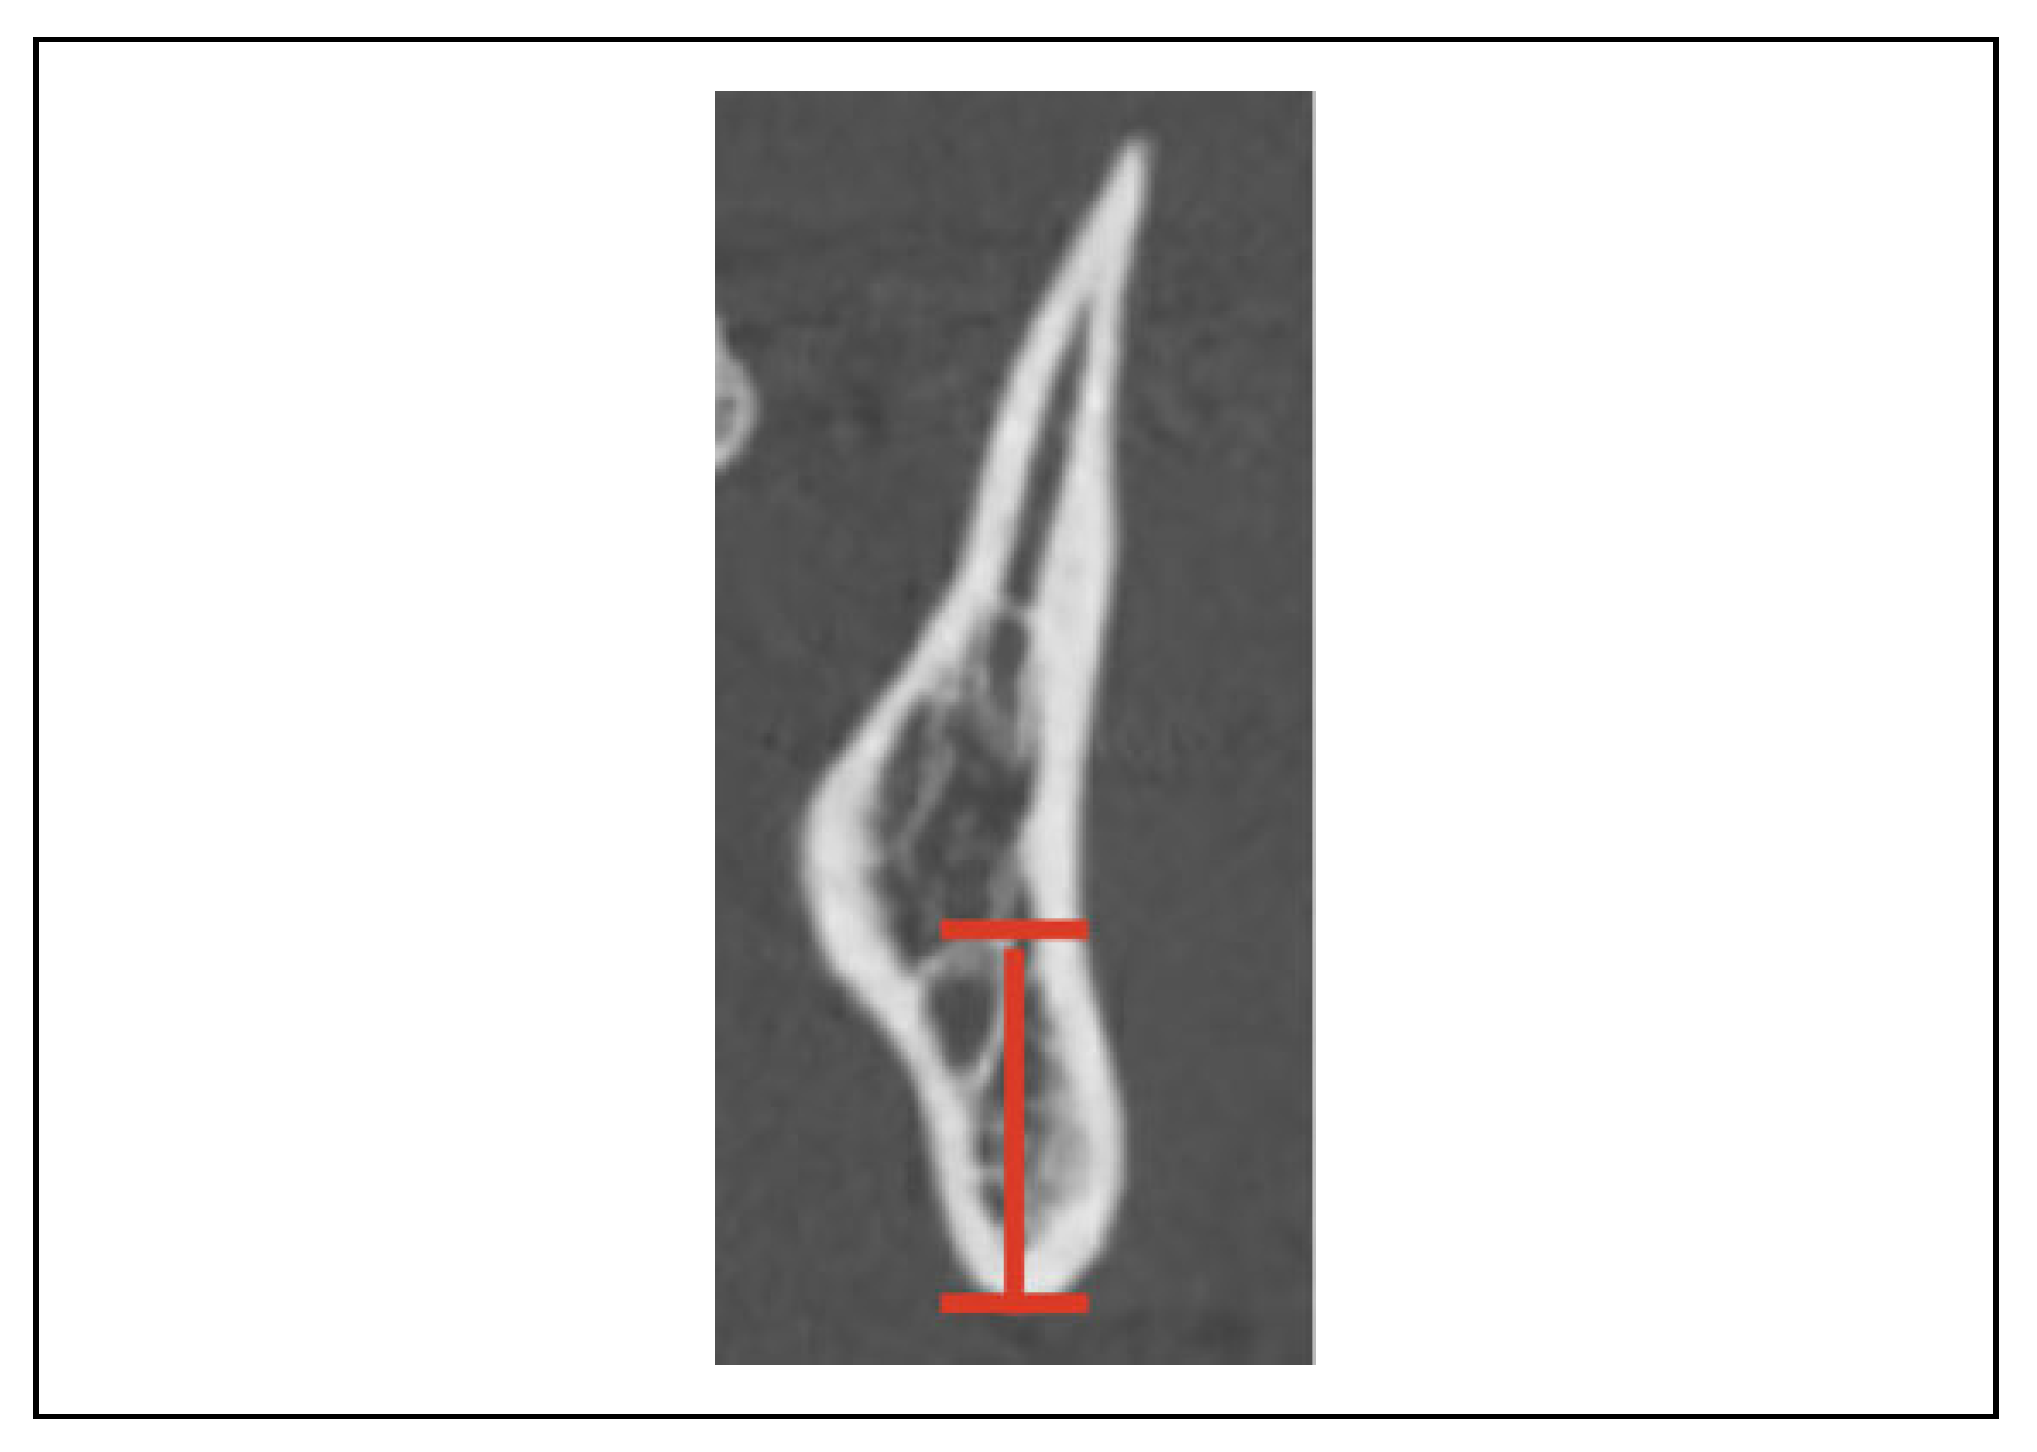

Is There a Safe Zone for Lateral Border Fixation of Mandibular Angle Fractures?

2. Methods

3. Results